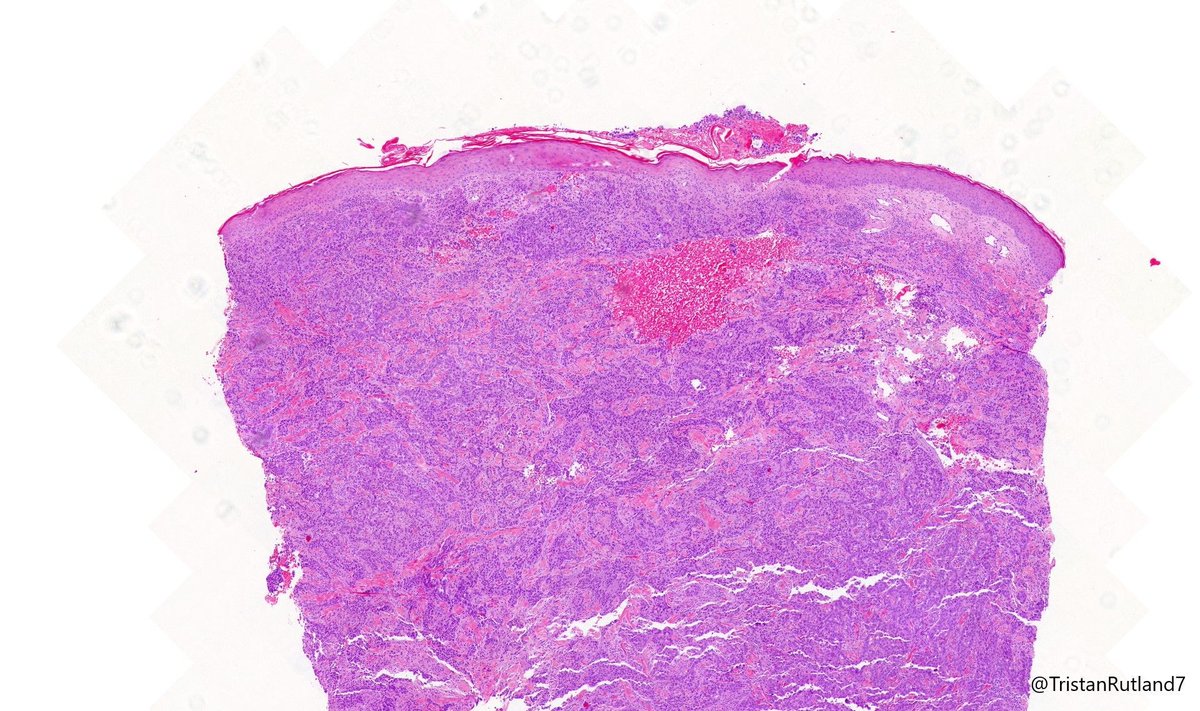

Tristan Rutland MBBS FRCPA IFCAP@TristanRutland7·

🔬𝐓𝐫𝐢𝐩𝐥𝐞-𝐍𝐞𝐠𝐚𝐭𝐢𝐯𝐞 𝐁𝐫𝐞𝐚𝐬𝐭 𝐂𝐚𝐫𝐜𝐢𝐧𝐨𝐦𝐚 (𝐍𝐒𝐓) 🔬 ⚠️ Pitfall alert 1️⃣ TNBCs can exhibit a range of morphologies, from metaplastic (sometimes resembling salivary gland tissue) to poorly differentiated or undifferentiated forms. 2️⃣ DCIS is usually absent. 3️⃣ GATA3 may be lost 4️⃣ SOX10 is usually positive (mimic melanoma). 5️⃣ 𝐃𝐢𝐚𝐠𝐧𝐨𝐬𝐭𝐢𝐜 𝐓𝐢𝐩: Always do a keratin and review patients history! #Breastpath #Dermpath #Pathtwitter #Pathresidents

Tristan Rutland MBBS FRCPA IFCAP tweet mediaTristan Rutland MBBS FRCPA IFCAP tweet mediaTristan Rutland MBBS FRCPA IFCAP tweet mediaTristan Rutland MBBS FRCPA IFCAP tweet media